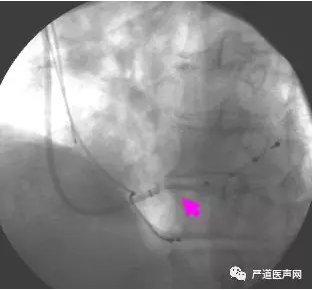

进冠状窦口后遇阻力:冒烟、导引钢丝

冠状窦口异常:大右房、低开口

● 处理:

➛ 选择直或多功能指引导管;

➛ 耐心、耐心、再耐心!